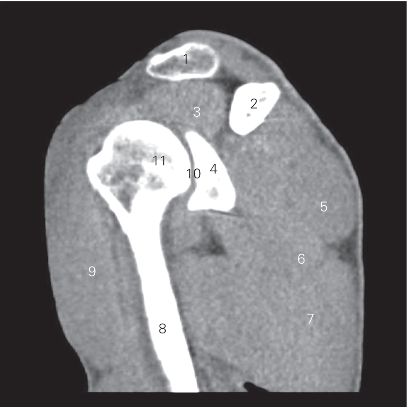

图4-2 经肩关节的冠状断层CT 图像(软组织窗)

1 斜方肌 trapezius 2 锁骨 clavicle

3 冈上肌 supraspinatus 4 肩关节 shoulder joint

5 关节盂 glenoid cavity 6 肩胛下肌 subscapularis

7 肋骨 rib 8 肱三头肌 triceps brachii

9 三角肌 deltoid 10 肱骨头 head of humerus

11 肩峰 acromion 12 肩锁关节 acromioclavicular joint